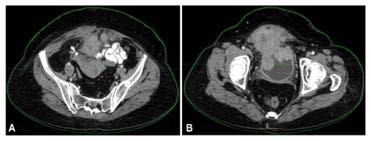

This image displays the targeted radiation fields covering the tumor bed and high-risk pelvic regions. The dose distribution was planned to maximize local control while minimizing exposure to nearby organs.

Figure 3: Radiation Dose Distribution Planning on CT for Bladder Carcinoma

Figure 3 illustrates the radiotherapy treatment planning performed after the patient’s radical anterior exenteration. The color-coded dose map shows how therapeutic radiation was precisely directed to the tumor bed and surrounding high-risk pelvic regions while protecting neighboring organs such as the bowel and remaining reproductive structures. The distribution pattern demonstrates adequate coverage of residual microscopic disease areas, supporting the goal of preventing local recurrence and improving long-term treatment outcomes.

Figure 4: PET-CT Radiation Therapy Planning for Bladder Carcinoma

Figure 4 shows the PET-CT–based planning image, which integrates metabolic activity with anatomical detail to refine the radiotherapy target area. Regions with increased tracer uptake indicate metabolically active tissue, helping clinicians identify areas at higher risk of harboring residual tumor cells. By combining PET and CT data, the treatment team ensured optimal precision in radiation delivery, minimizing healthy tissue exposure while maximizing tumor control. This advanced planning approach strengthens both therapeutic effectiveness and patient safety.